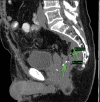

Management of the acute anastomotic leak is complex and patient-specific. Clinically stable patients often benefit from a nonoperative approach utilizing antibiotics with or without percutaneous drainage. Clinically unstable patients or nonresponders to conservative management require operative intervention. Surgical management is dictated by the degree of contamination and inflammation but includes drainage with proximal diversion, anastomotic resection with end-stoma creation, or reanastomosis with proximal diversion. Newer therapies, including colorectal stenting, vacuum-assisted rectal drainage, and endoscopic clipping, have also been described.